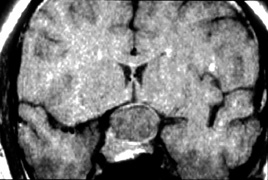

Prognosis for recovery depends on etiology, age of onset, and severity of brain damage (Fig. 7). Although such children often remain visually handicapped, dramatic recovery may ensue occasionally.36 Cortical visual loss from perinatal hypoxia/ischemia has a particularly poor prognosis if congenital, but up to a 70% recovery rate if acquired.37 Although hydrocephalus, brain dysgenesis, and infections may produce cortical visual loss, by far the most common cause of CVI in the developed world is perinatal hypoxia. In term infants, damage primarily affects the watershed areas of the cerebral cortex (frontal and parieto-occipital regions). In premature babies, however, the damage is predominantly periventricular. Age-related differences in the developing intracranial vascular systems may account for the disparate sites of injury. The watershed zone in term infants (and adults) is at the parieto-occipital junction, whereas in preterm infants it is in the subcortical area.38

Fig. 7. Computed tomography of child with cortical visual impairment resulting from congenital hydrocephalus. Note significant ex vacuo dilatation of the ventricles posteriorly, with shunt catheter in place.